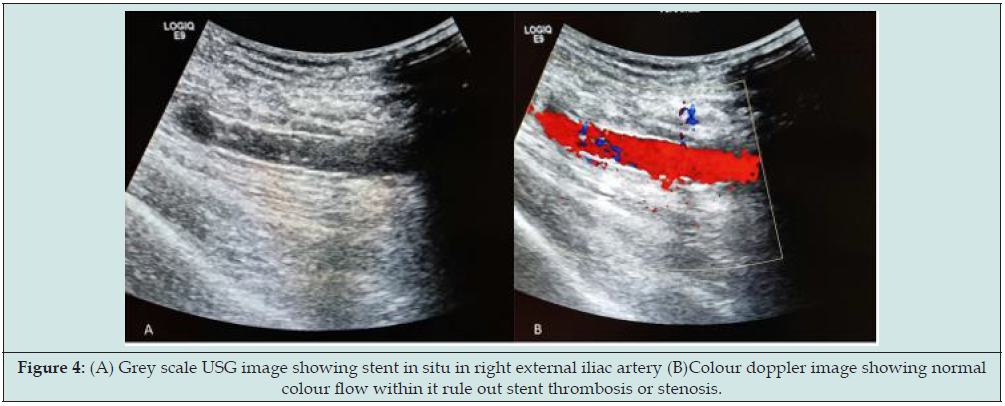

CT angiography findings were small pseudoaneurysm (measuring 11x8x6mm in size and neck measuring 2mm) was seen arising from right external iliac artery (Figure 3). Hemorrhage containing sinus tract (measuring 30mm in length and 4mm in diameter) was also demonstrated in right iliac fossa extending from skin to pseudoaneurysm within extraperitoneal compartment. So final diagnosis of contained ruptured right external iliac artery pseudoaneurysm following post-transplant nephrectomy was made. Patient was treated with endovascular stenting through right femoral approach. A 10x38mm size balloon mounted covered stent was placed in the right external iliac artery covering pseudoaneurysm. No filling of pseudoaneurysm was seen in completion angiography. There were no post-procedural complications and patient was discharged 2 days after the procedure. No pseudoaneurysm demonstrated in colour doppler study with patent iliofemoral vessels on 1 month follow up (Figure 4).

Figure 4: (A) Grey scale USG image showing stent in situ in right external iliac artery (B)Colour doppler image showing normal colour flow within it rule out stent thrombosis or stenosis.